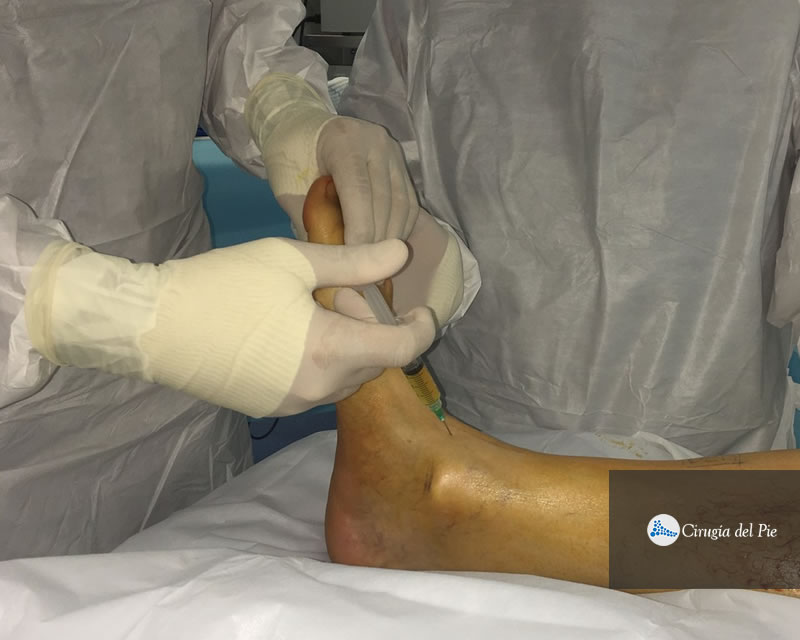

Se obtiene de la sangre del propio paciente. La muestra es procesada en forma específica en una centrífuga, separando las distintas fracciones de la sangre. Una de ellas, es el plasma con concentrado de plaquetas. La característica principal de esta fracción es que presenta una gran cantidad de factores de crecimiento que promueven la migración y diferenciación celular para la reparación de los tejidos. Este material puede procesarse para ser utilizado en forma líquida o gelatinosa, pudiendo ser aplicado en tratamientos de cura avanzada de heridas y úlceras, también a nivel muscular, tendinoso, ligamentario y fracturas, como así también en forma intraarticular. Habitualmente lo hacemos en forma ambulatoria.

Plasma rico en plaquetas Dr Masaragian